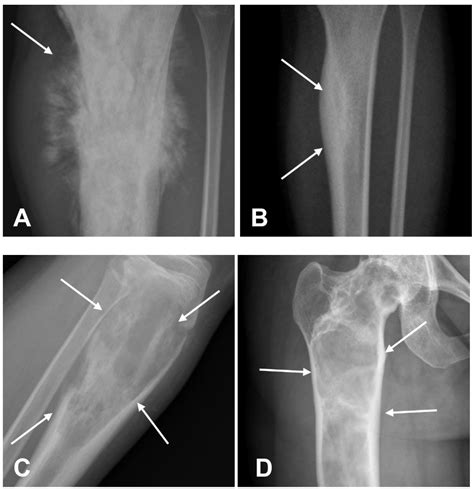

When a patient presents with persistent, unexplained bone pain, especially in children, adolescents, or young adults, medical professionals often prioritize imaging to rule out malignancies. Among the various diagnostic tools available, the Osteosarcoma X Ray is frequently the first line of investigation. Osteosarcoma is the most common primary bone cancer in children and adolescents, and while X-rays are not definitive for diagnosis on their own, they provide crucial radiographic features that help radiologists and orthopedic oncologists identify suspicious lesions. Early detection is paramount for improving patient outcomes, making the interpretation of these initial radiographs a vital component of the diagnostic journey.

Radiographic imaging acts as a gateway to further diagnostic procedures, such as biopsies and MRI scans. When a physician suspects a bone tumor, an Osteosarcoma X Ray is ordered to evaluate the integrity of the bone, the extent of tumor involvement, and the relationship between the tumor and surrounding soft tissues.

The primary goal of the initial X-ray is to assess for "aggressive" features that distinguish a potentially malignant tumor from a benign one. Radiologists look for specific patterns of bone destruction and the body’s reaction to the lesion. While these imaging findings can be highly suggestive, they must always be correlated with the patient's clinical history, physical examination, and subsequent pathological analysis.

Common radiographic findings that might trigger a suspicion of osteosarcoma include:

• Cortical Destruction: A lack of well-defined borders indicating the tumor is aggressively breaking through the bone shell.

• Sunburst Pattern: Radiating spicules of bone formation that extend outward from the tumor into the soft tissue.

• Codman’s Triangle: A triangular formation of new bone that occurs when the tumor grows faster than the periosteum (the outer covering of the bone) can form new bone, resulting in an elevation of the periosteum.

• Soft Tissue Mass: Shadows outside the bone that suggest the tumor has breached the cortical bone and is invading the surrounding soft tissues.

Interpreting an Osteosarcoma X Ray requires a nuanced eye. Osteosarcoma is heterogeneous, meaning it can present in several different ways depending on its subtype and location. The appearance of the lesion often depends on whether it is predominantly osteoblastic (bone-forming) or osteolytic (bone-destroying).